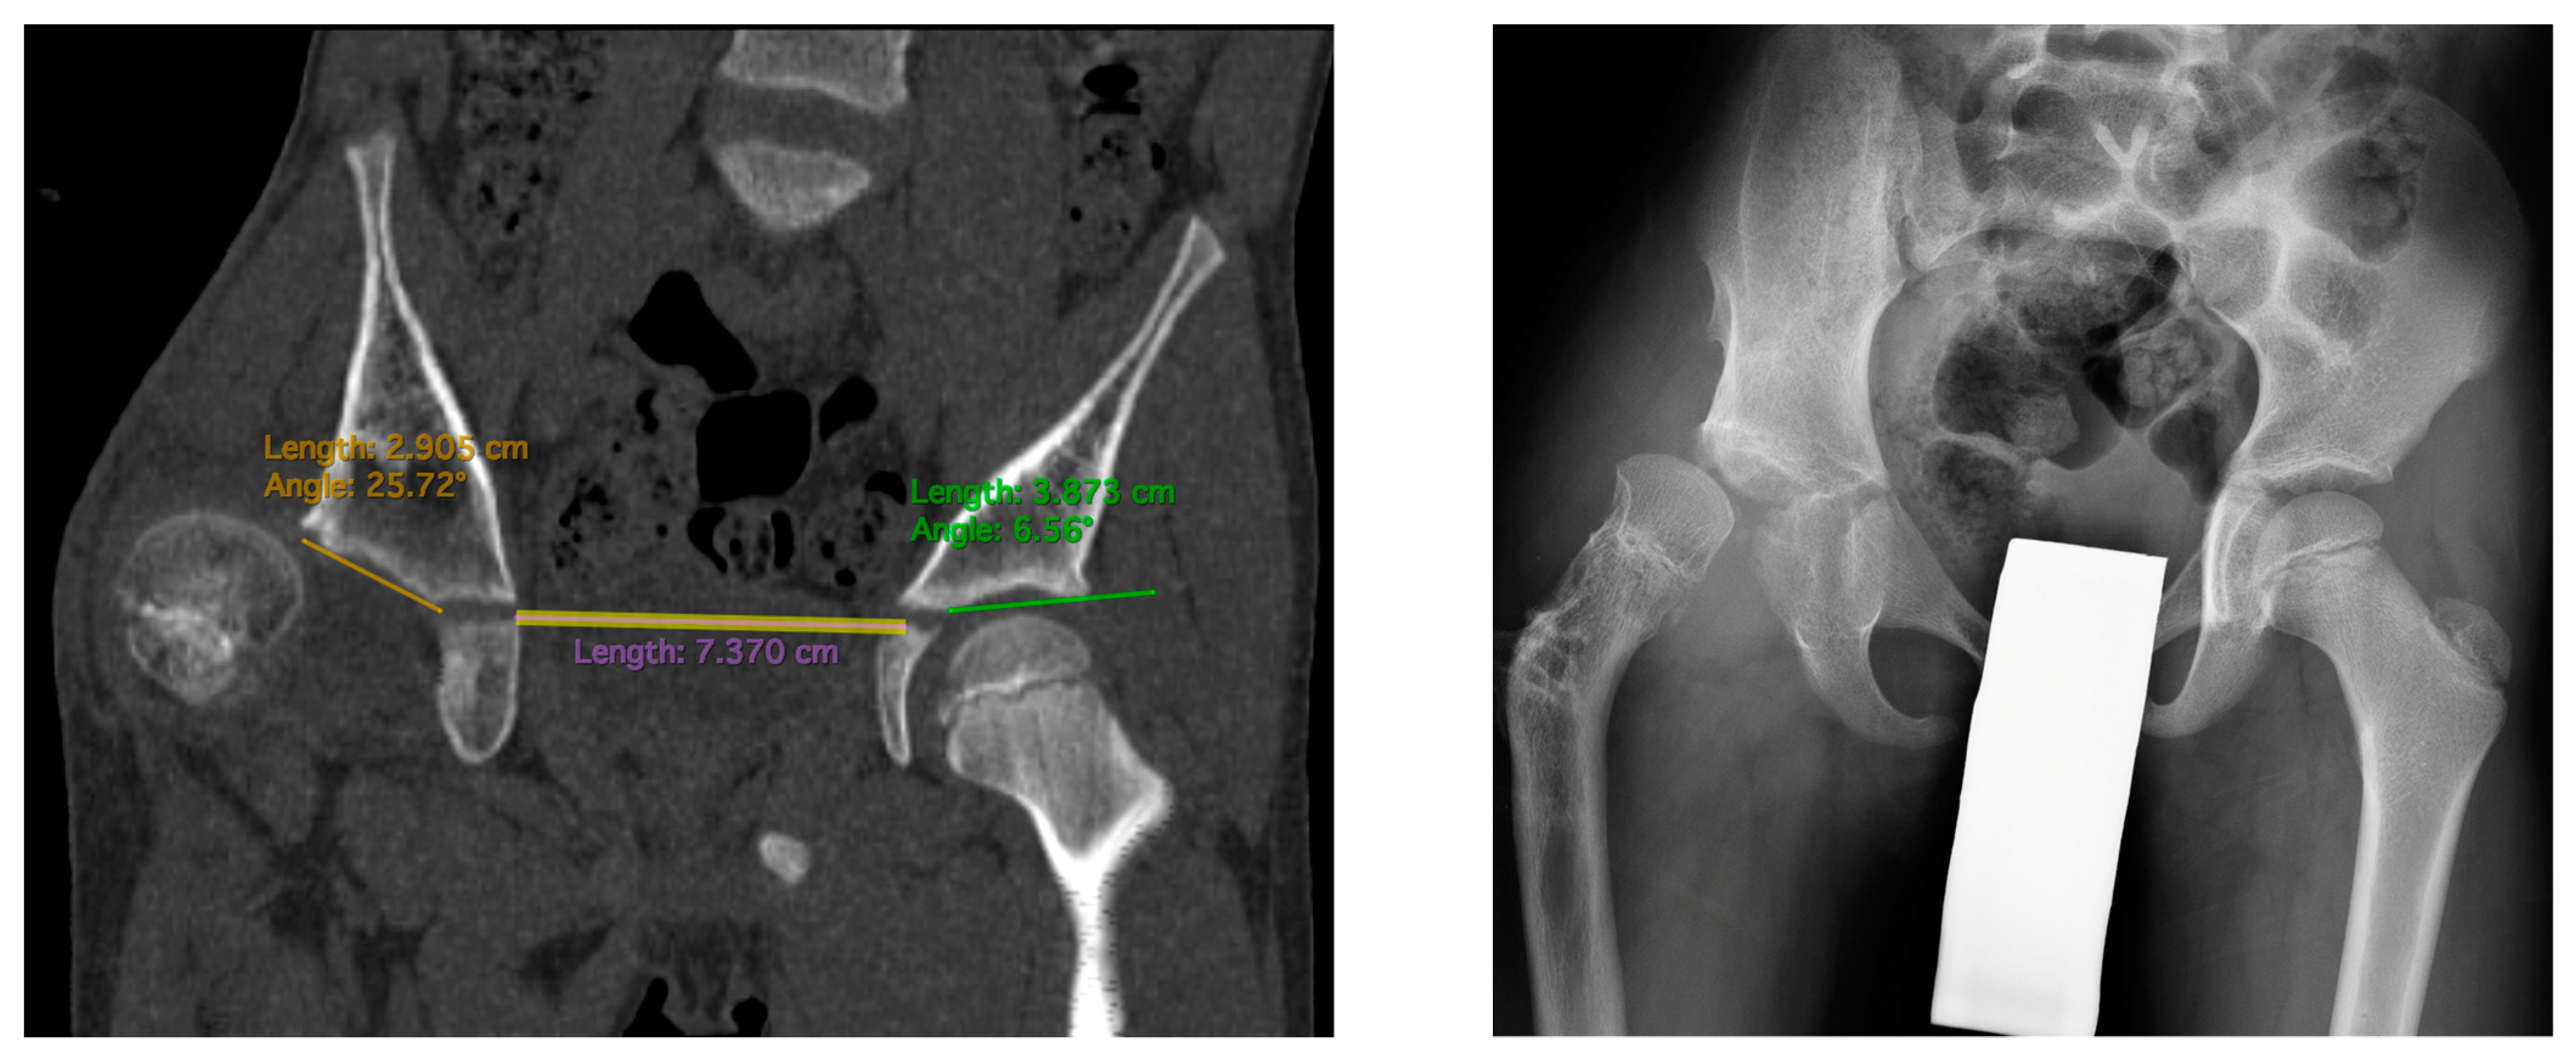

Figure 3.

CT scan showing AIm measurements (left): 24 deg on the affected side vs. 6 deg on the healthy side. Hip radiogram of the same patient with hip joint dislocation (right).

All five included patients presented a deficit of the coverage of the posterior part of the acetabulum. These patients presented a normal Acetabular Inclination angle on standard hip radiograms and a pathological high Acetabular Inclination angle measured in the posterior part of the acetabulum on CT scan (>25 deg); the difference between CT and RTG for the AI measured in the posterior part was statistically significant (28.3 deg vs. 19.8 deg, p < 0.01). Another finding was that the AI measured in the anterior, middle, and posterior parts of the acetabulum were significantly different in the CFD hip joint (16.2 deg vs. 22.4 deg vs. 28.3 deg, p < 0.01), with no such difference at the healthy side. The difference in AI measured in the posterior vs. anterior part of the acetabulum was 11.1 deg in the CFD unstable hip joint, and it was significantly higher than on the healthy side (11.1 deg vs. 3.0 deg, p < 0.05). CT analysis is shown in Table 8. A CT scan of a patient with hip instability is shown in Figure 2 and Figure 3.